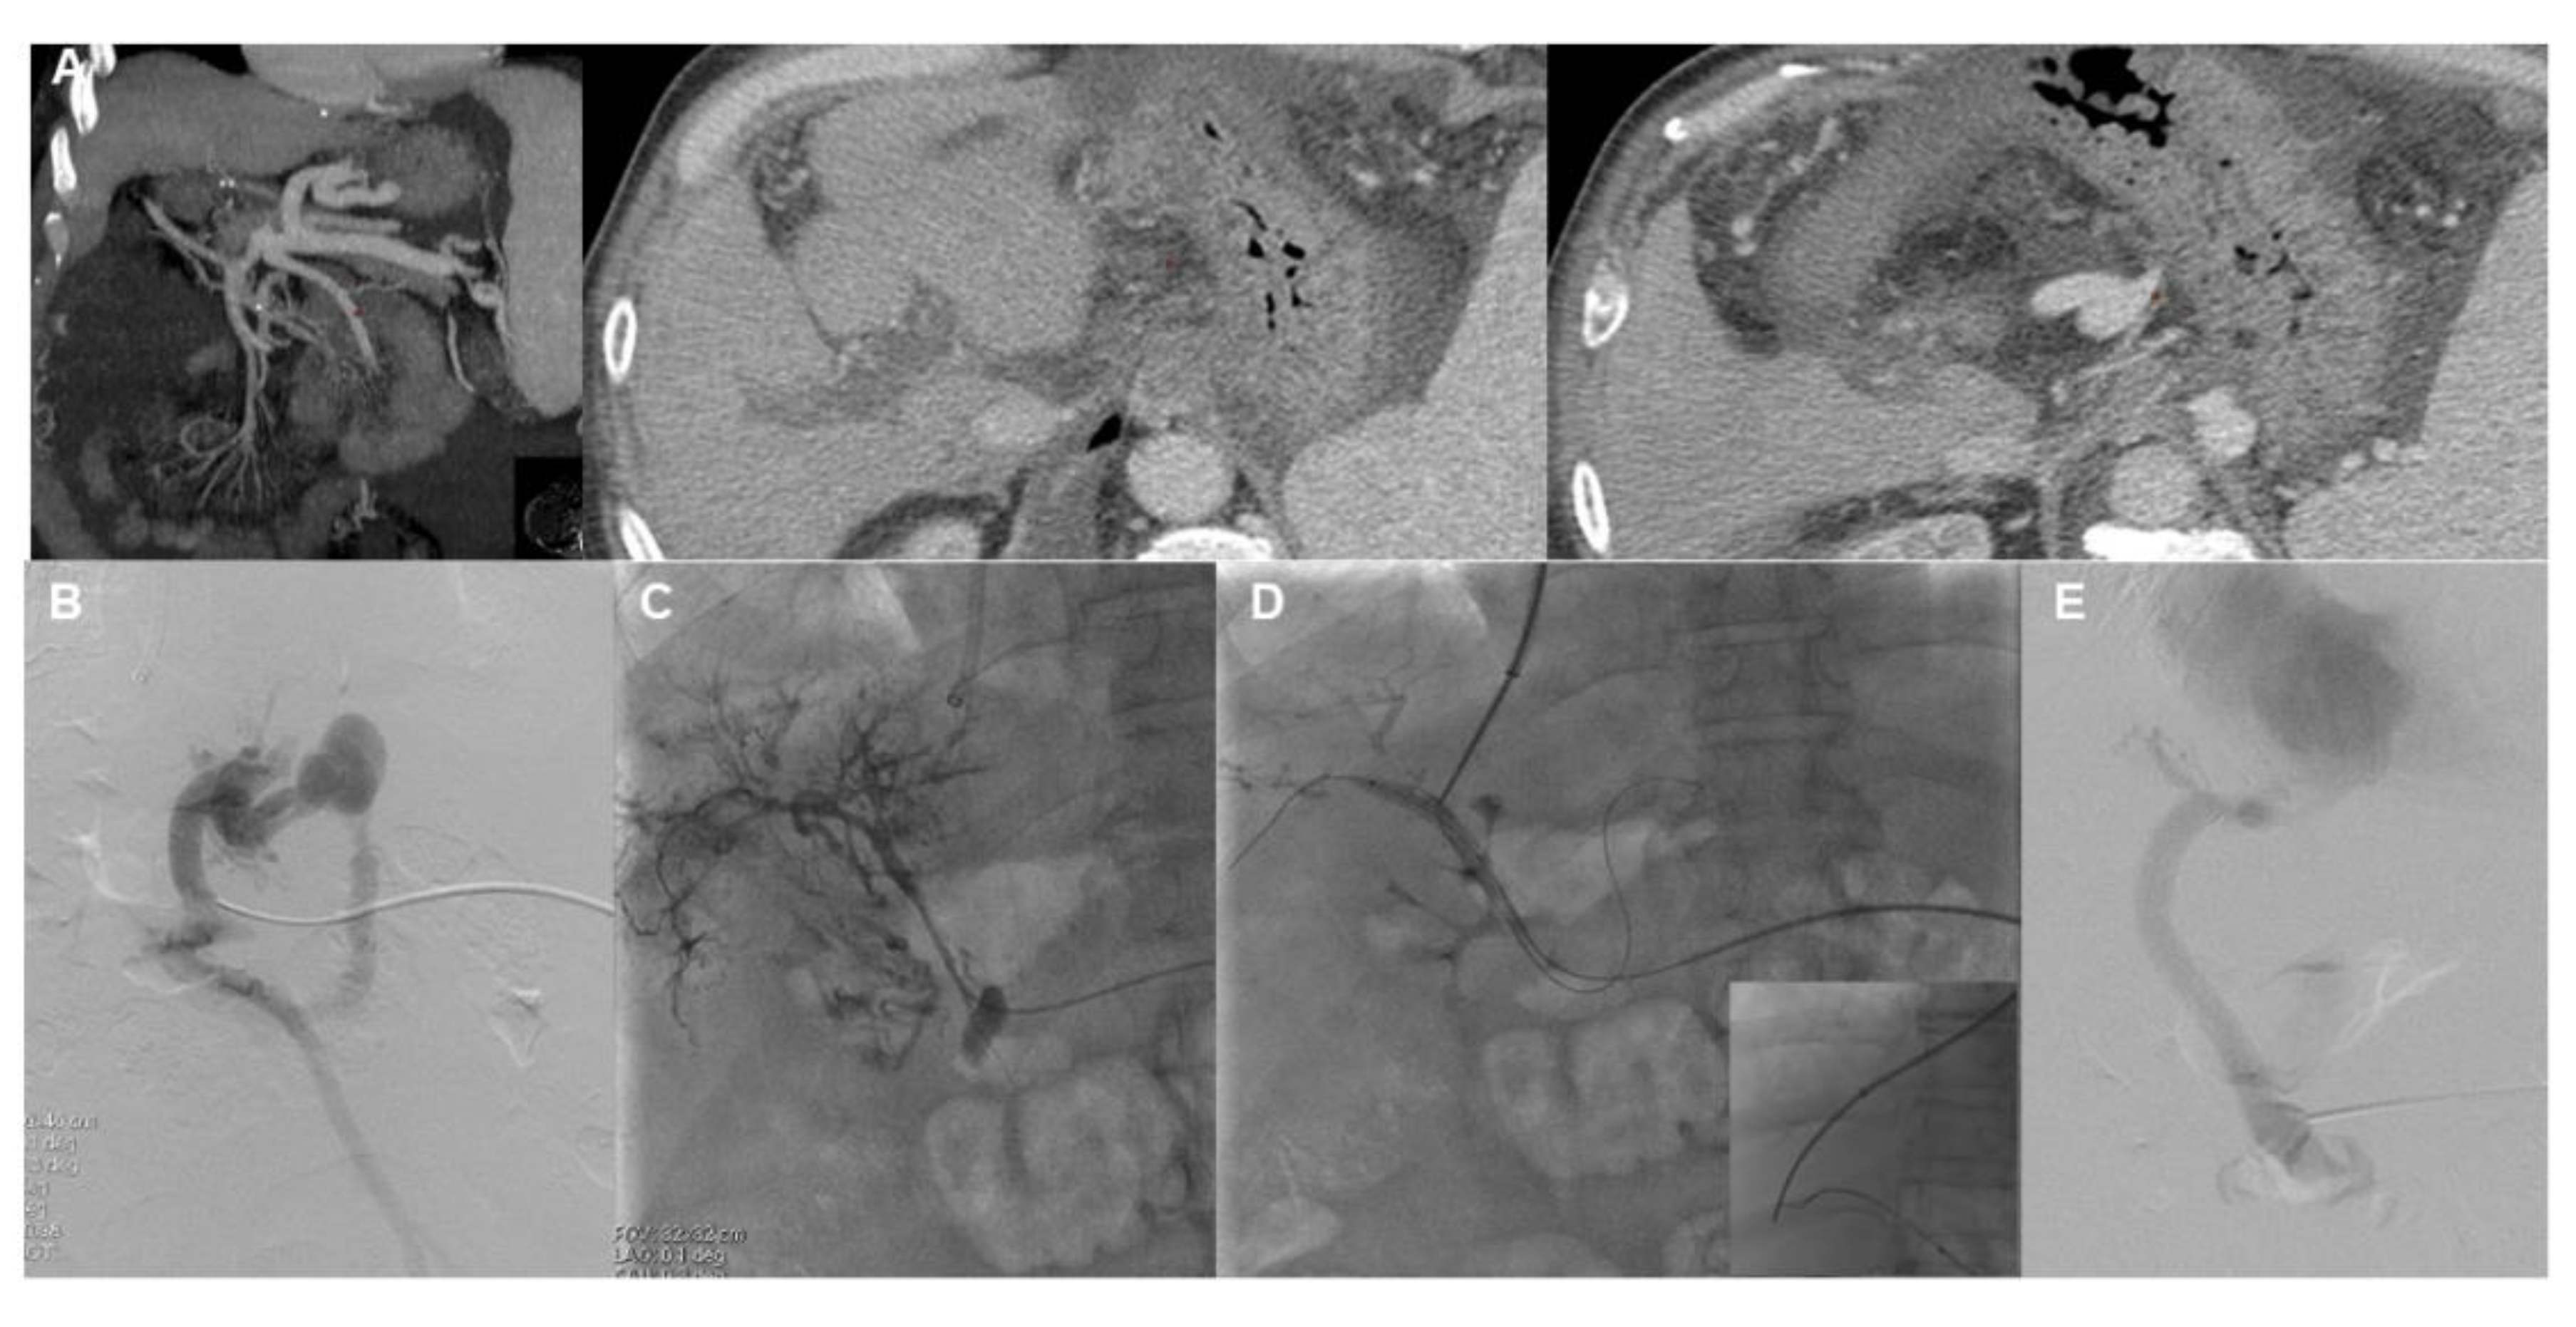

- Chen, Y.; Ye, P.; Li, Y.; Ma, S.; Zhao, J.; Zeng, Q. Percutaneous transhepatic balloon-assisted transjugular intrahepatic portosystemic shunt for chronic, totally occluded, portal vein thrombosis with symptomatic portal hypertension: Procedure technique, safety, and clinical applications. Eur. Radiol. 2015, 25, 3431–3437. [Google Scholar] [CrossRef]

- Entezari, P.; Riaz, A.; Thornburg, B.; Salem, R. Percutaneous Ultrasound-Guided Superior and Inferior Mesenteric Vein Access for Portal Vein Recanalization-Transjugular Intrahepatic Portosystemic Shunt: A Case Series. Cardiovasc. Intervent. Radiol. 2021, 44, 496–499. [Google Scholar] [CrossRef]

- Steffen, D.A.; Najafi, A.; Binkert, C.A. Safety of Percutaneous Transmesenteric and Transsplenic Access for Portosystemic Shunt Creation in Patients with Portal Vein Obstruction: Single-Center Experience and Review of Literature. Cardiovasc. Intervent. Radiol. 2023, 46, 1401–1406. [Google Scholar] [CrossRef]

- Klinger, C.; Riecken, B.; Schmidt, A.; De Gottardi, A.; Meier, B.; Bosch, J.; Caca, K. Transjugular portal vein recanalization with creation of intrahepatic portosystemic shunt (PVR-TIPS) in patients with chronic non-cirrhotic, non-malignant portal vein thrombosis. Z. Gastroenterol. 2018, 56, 221–237. [Google Scholar] [CrossRef]

- Knight, G.M.; Clark, J.; Boike, J.R.; Maddur, H.; Ganger, D.R.; Talwar, A.; Riaz, A.; Desai, K.; Mouli, S.; Hohlastos, E.; et al. TIPS for Adults Without Cirrhosis With Chronic Mesenteric Venous Thrombosis and EHPVO Refractory to Standard-of-Care Therapy. Hepatology 2021, 74, 2735–2744. [Google Scholar] [CrossRef]